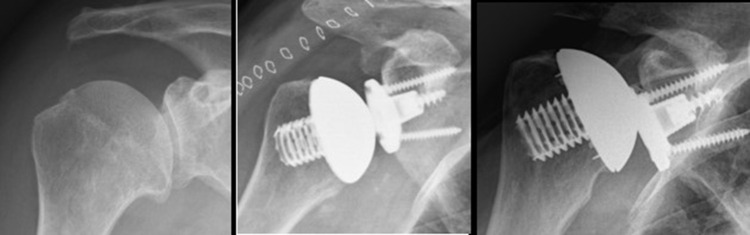

Background: Historically, Metal-Backed (MB) glenoid components in anatomical total Shoulder arthroplasty (aTSA) are prone to failure primarily due to loosening between the metal and bony surface. However, newer generations of MB glenoid components have performed well in reverse shoulder arthroplasty (RSA), with convertibility being considered to be the most significant benefit of MB components. Theoretically, MB components may be a viable option in "Rotator cuff at risk" cases. The aim of this study is to compare revisions versus revision-free survivorship and highlight problems associated with using convertible MB glenoid components in aTSA.

Methods: Between December 2015 and September 2018, aTSA was performed on 30 patients utilizing 32 implants with convertible MB glenoid (two patients were operated bilaterally). The first investigation was performed at a mean of 55.9 months (43-76) by search in the national registry for revisions with twelve cases. The second FU on all remaining patients without revisions was conducted at a mean of 54.9 months (46-71) through physical examination with fourteen patients (sixteen implants), with four patients missing. Demographic data, indications, complications, revisions, and re-operations were recorded for each patient.

Results: High rates of complications led to revisions or re-operation in aTSA in combination with MB (15/32). Seven problems were associated with polyethylene (PE), which included loosening, disengagement, or wear. Eight complications were not directly associated with the MB component. There was one with loosening on the metal-bone interface side. Conversion to RSA was possible in three cases, and secondary cuff failure was seen once. High infection rates (2/32) led to a different strategy for antibiotics and preoperative preparations.

Conclusion: MB glenoid components caused unacceptably high complication and revision rates in aTSA. PE wear, disengagement, or loosening were the main reasons for revisions. Therefore, procedures with MB glenoid components were abandoned in aTSA.